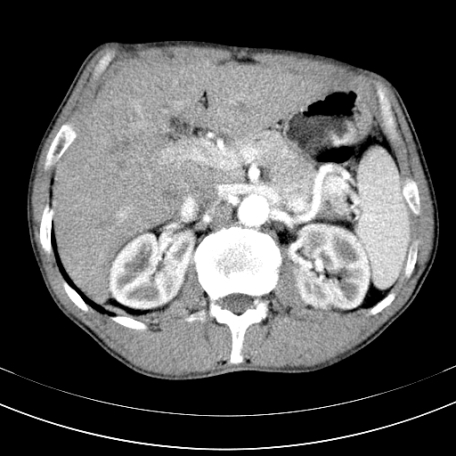

标题: CT21441:男55岁,上腹部胀痛半年余,请老师们看看是后腹膜淋巴 [打印本页]

标题: CT21441:男55岁,上腹部胀痛半年余,请老师们看看是后腹膜淋巴

腹主动脉右侧有一个,有肿瘤病史吗?

腹膜后淋巴结肿大,原因待查。